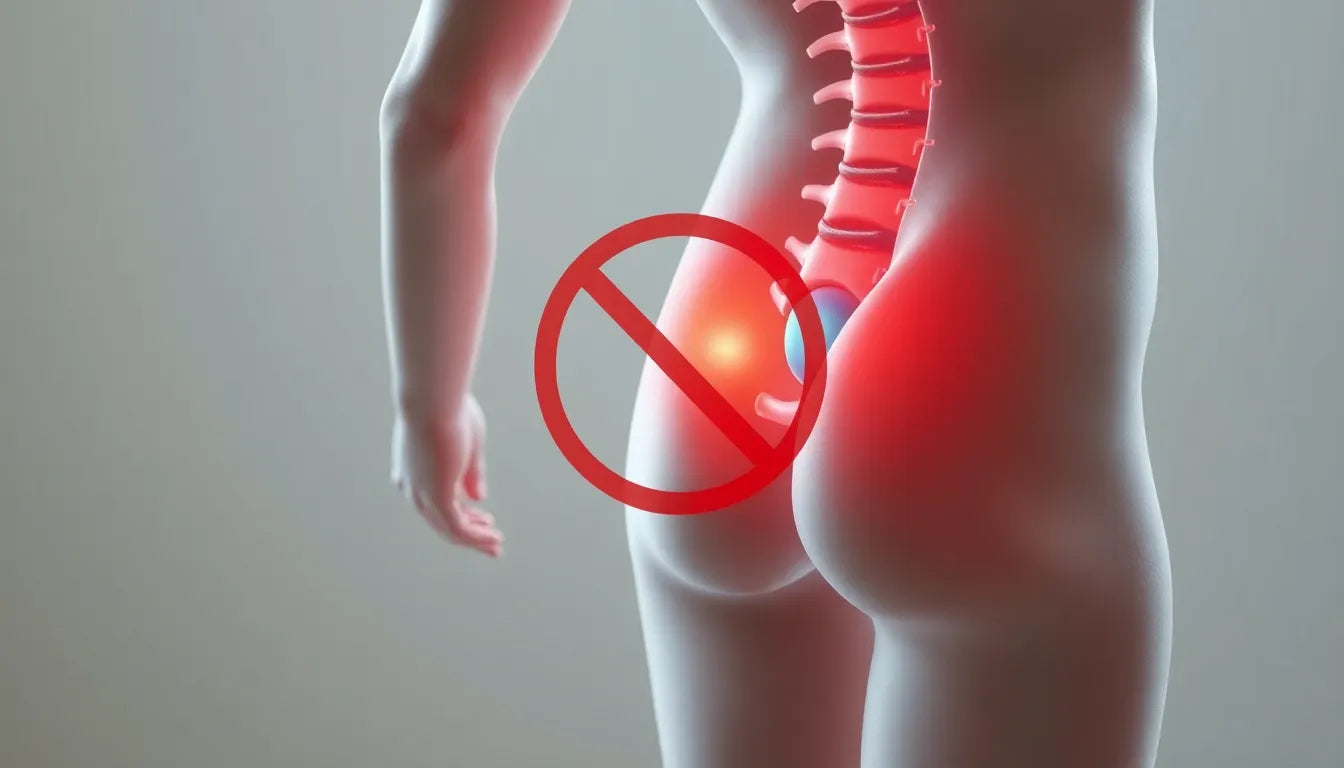

Ontsnap aan de pijn: verlichting voor douleur nerf sciatique fessier

Sciatalgie, veroorzaakt door een geïrriteerde of samengedrukte nerf sciatique, leidt tot pijn in de fessier en benen en beïnvloedt miljoenen wereldwijd. Symptomen variëren van brandende pijn tot sp...